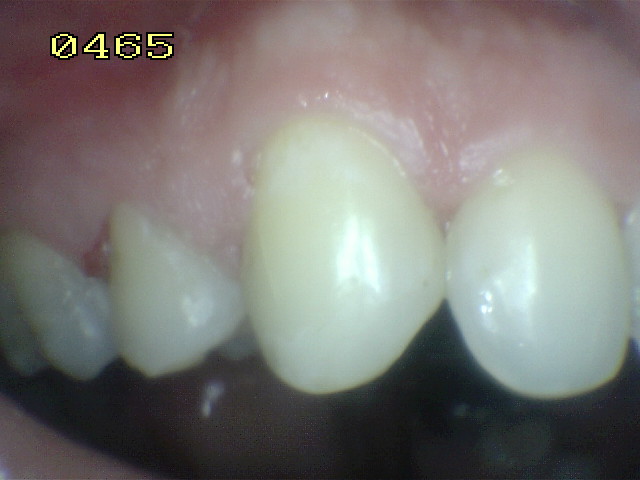

Código 3 (Caries moderada) in vitro. Los códigos 3 in vivo debe ser sellado para evitar el avance del proceso carioso. (MNO)

Código 4 (Caries moderada) in vitro. Los códigos 4 in vivo deben ser tratados en forma operatoria con preservación dental (MOPD), porque presentan dentina infectada.